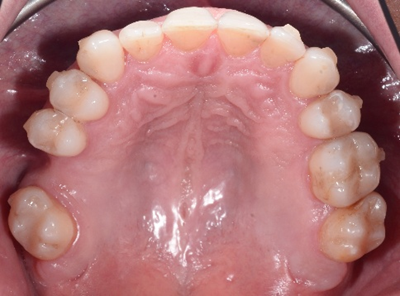

In this orthodontic case, Dr. Timpu-Dascalu addressed an anterior crossbite, a misalignment that can lead to functional issues and aesthetic concerns.

To correct the anterior cross-bite, the doctor utilized a comprehensive approach focusing on biomechanics to ensure precise tooth movement. This approach allowed her to achieve a stable and functional occlusion, improving both the patient’s bite and smile.

The treatment focused on correcting the anterior crossbite while simultaneously addressing both transversal and sagittal discrepancies. The primary goals were to expand both the upper and lower arches, derotate the molars, and address the uncontrolled tipping of tooth 12. Spark 20 package was selected to achieve the orthodontic goals. The treatment plan was meticulously developed using Spark’s Approver software.